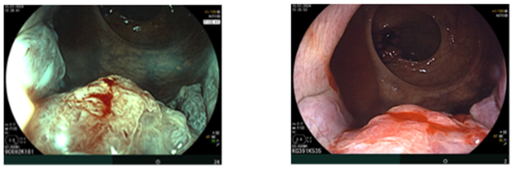

Nội soi đại–trực tràng (07/2024):

Ghi nhận hai tổn thương u sùi ở trực tràng, cách rìa hậu môn khoảng 5 cm và khoảng 10 cm. Tổn thương “phía trong” chiếm gần hết lòng trực tràng; tổn thương “phía ngoài” kích thước khoảng 3,0 cm. Ống hậu môn có đám tổn thương gồ ghề loang lổ.

Hình 1: Tổn thương u sùi ở trực tràng

Hình 2: Tổn thương gồ ghề loang lổ ở ống hậu môn